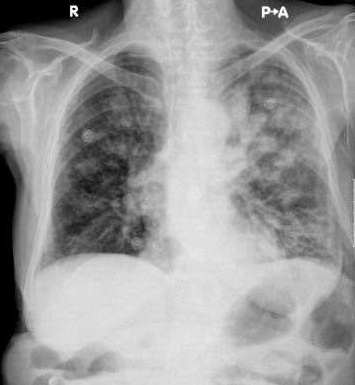

以下是引用37度在2009-9-12 11:54:00的发言:[br][br] [br] 支气管扩张合并混合型感染 [br] [br]

以下是引用dyqct在2009-9-12 8:42:00的发言:[br]慢性支气管炎合并间质纤维化、肺气肿、支气管扩张、感染。建议ct进一步检查。

以下是引用黑白光影在2009-9-12 16:43:00的发言:[br]慢支并感染(霉菌?)